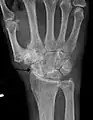

Diagnosis is made with reasonable certainty based on history and clinical examination.[51][52] X-rays may confirm the diagnosis. The typical changes seen on X-ray include: joint space narrowing, subchondral sclerosis (increased bone formation around the joint), subchondral cyst formation, and osteophytes.[53] Plain films may not correlate with the findings on physical examination or with the degree of pain.[54]

Severe osteoarthritis and osteopenia of the carpal joint and 1st carpometacarpal joint